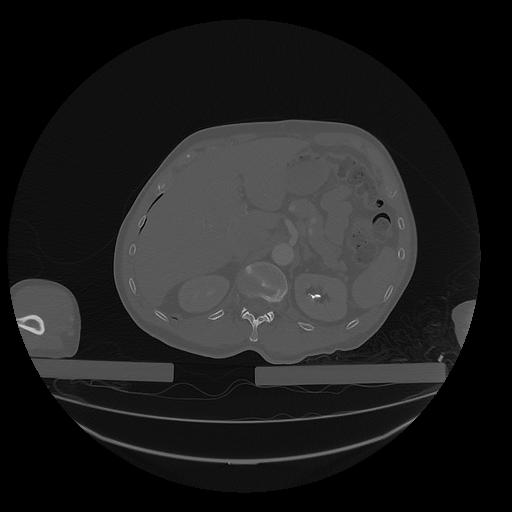

31 PULMON,CE,Vol,1.0,PULMON,,